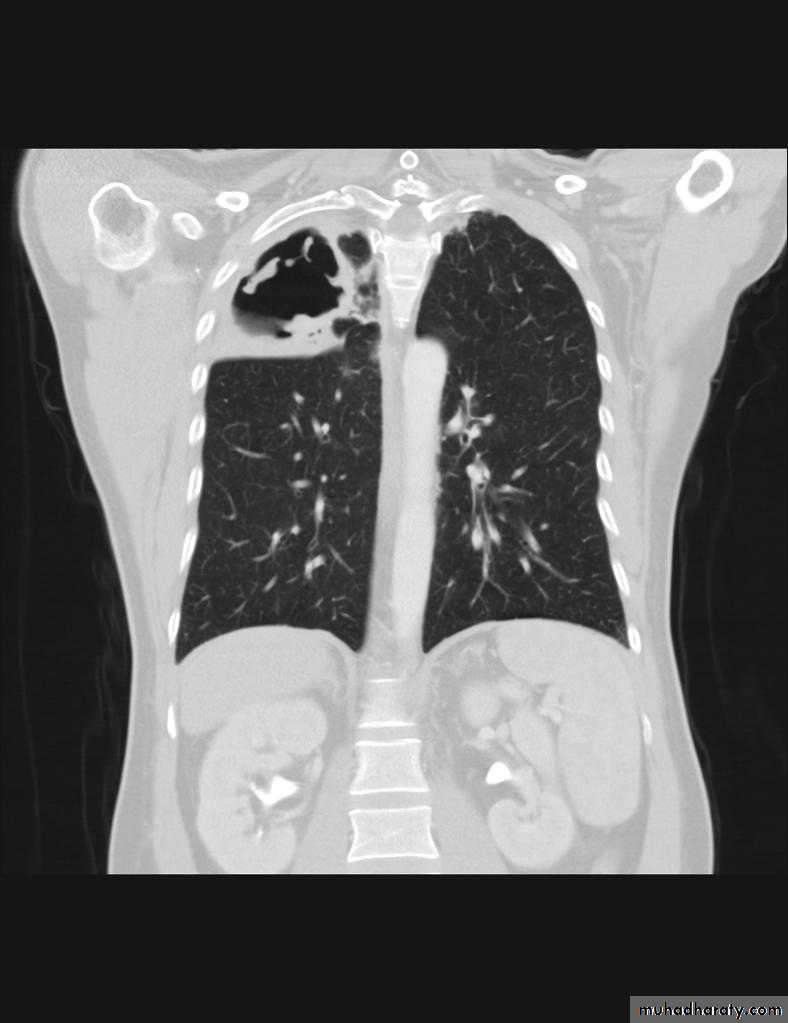

TB lung abscess

67.upper apical TB cavity68.Aspergilloma